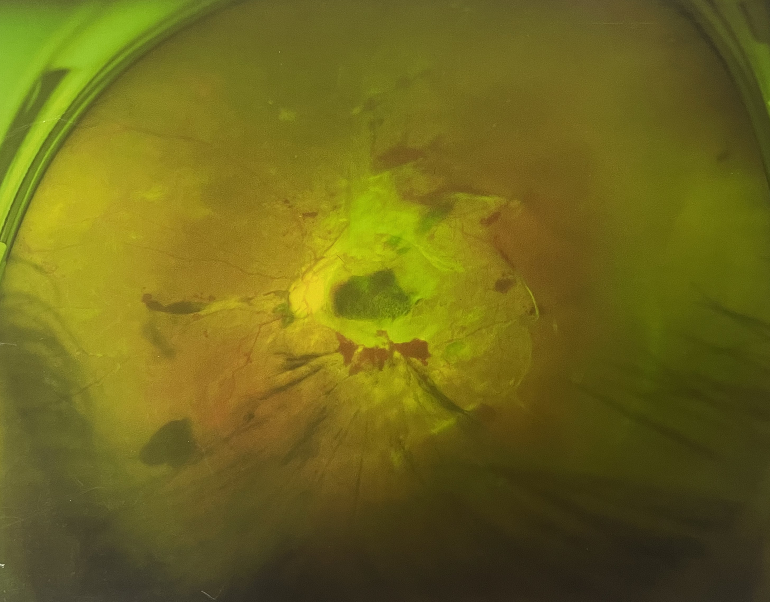

眼底出血一般多久能好?眼底出血可以由眼科本身疾病引起,常見的是視網(wǎng)膜靜脈阻塞、糖尿病視網(wǎng)膜病變、中心性滲出性視網(wǎng)膜病變、視網(wǎng)膜動脈硬化、老年性黃斑病變、視網(wǎng)膜靜脈周圍炎。

另外,眼底出血還可以由全身疾病引起,比如糖尿病可以引起眼底出血,高血壓也會引起眼底出血,還有嚴重的腎病,血液方面的疾病都可以導致眼底出血。

眼底出血一般多久能好?眼底出血如果是輕癥,時間較短的患者大約3-6個月可以恢復(fù),如果是重癥或者病程較長的患者,可能要持續(xù)1年,甚至2年時間。

眼底出血一般多久能好?眼底出血是醫(yī)生用檢眼鏡才能看到,患者和其他人看不見。眼底出血不是單獨的病,一般來說是由眼科本身疾病造成,還可以由全身疾病造成。比如常見的視網(wǎng)膜靜脈阻塞、糖尿病視網(wǎng)膜病變等引起的眼底出血較常見。眼底出血一般多久能好?所以眼底出血的出血吸收時間也不一樣,要根據(jù)病情輕重決定其預(yù)后,出血吸收時間也不一樣。